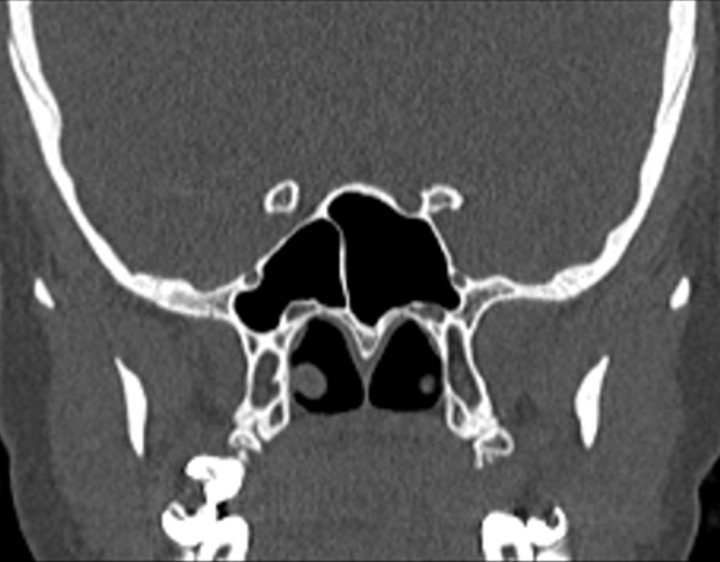

Click any image for labels.